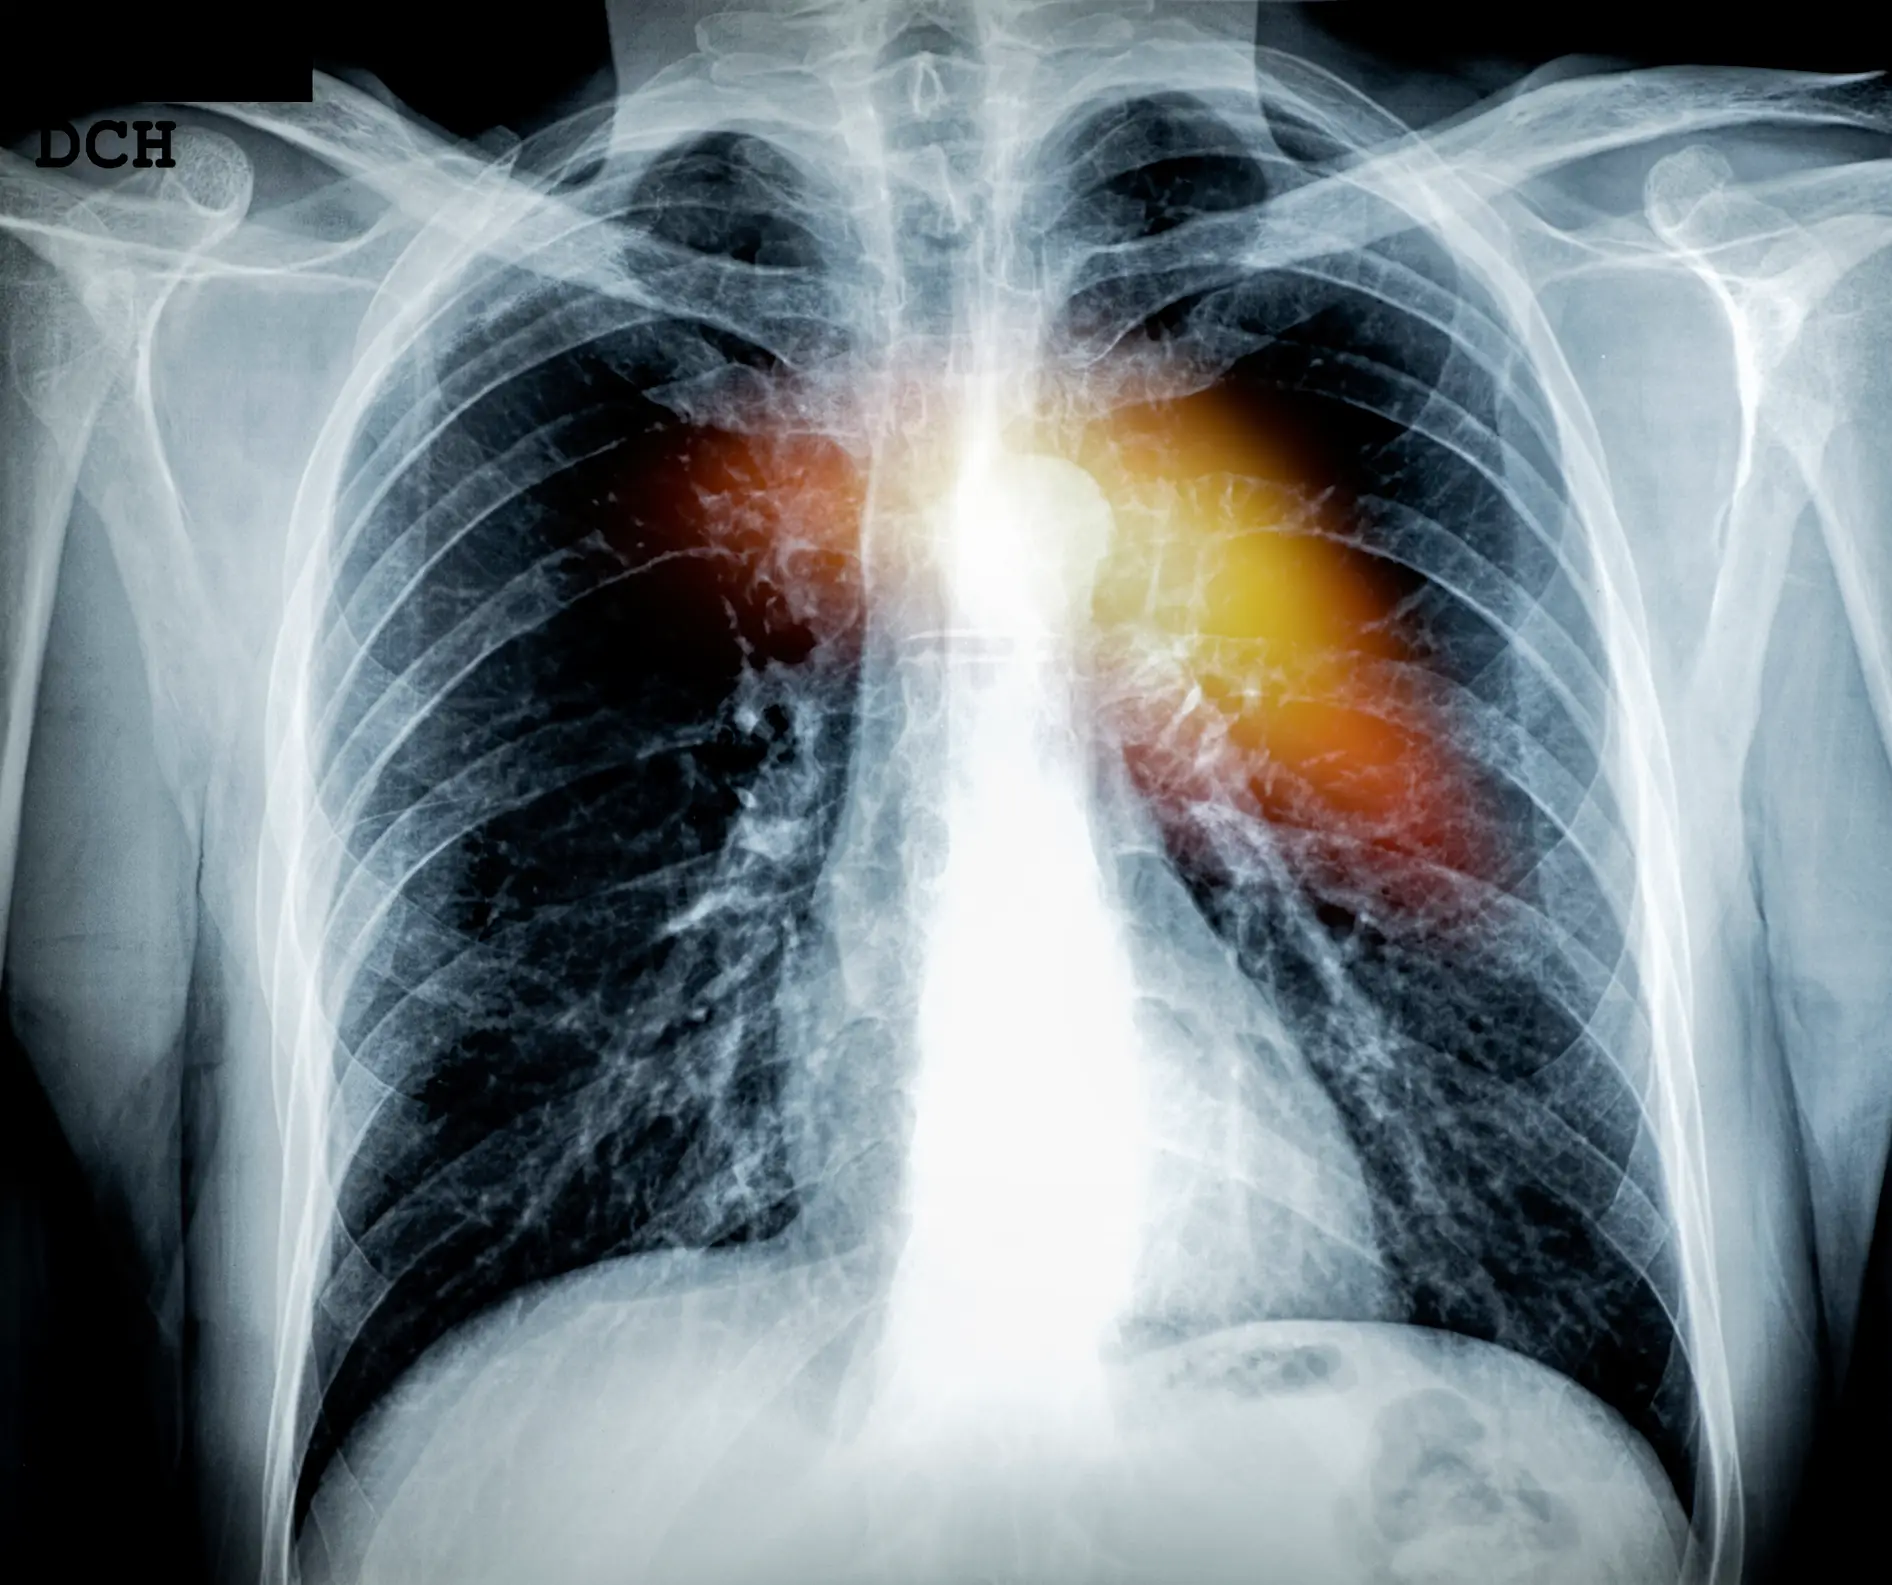

The lad explained it was eventually determined he’d suffered a heart attack and he remembered feeling a ‘pressure on your chest and in your arms’.